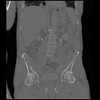

6 CUERPO,CE,Coronal,3.000,CUERPO,Coronal,